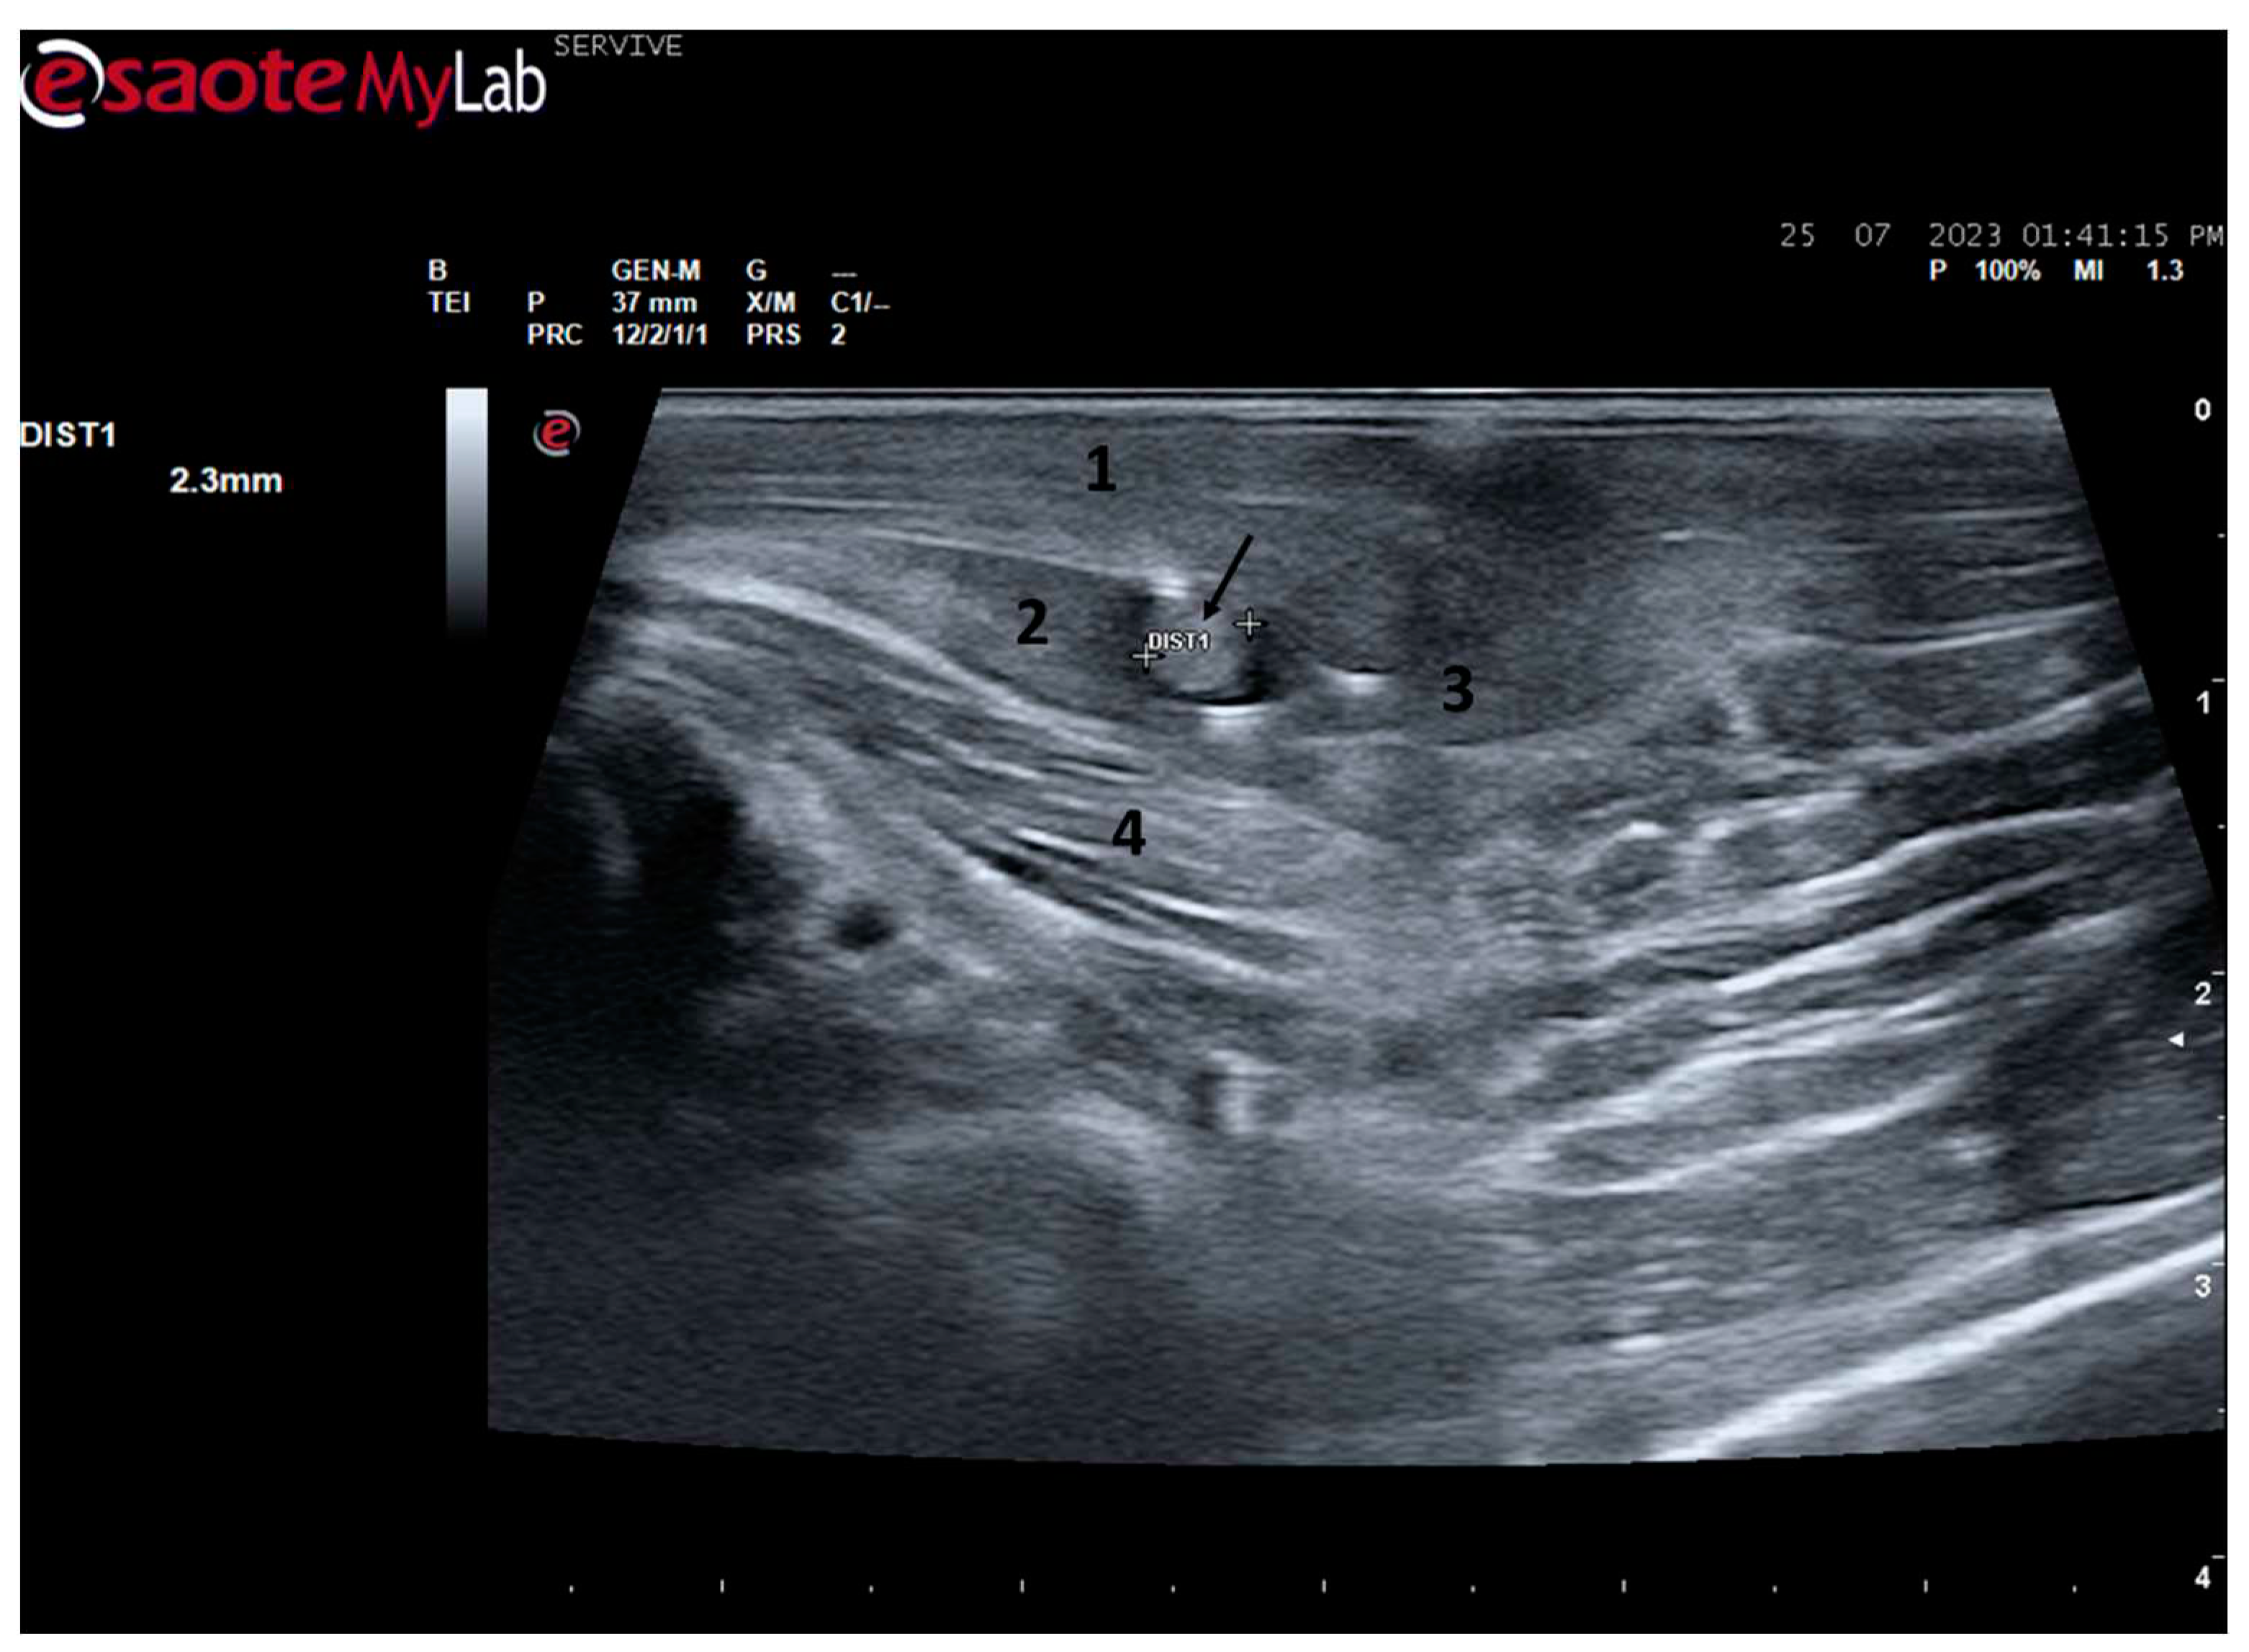

Figure 3.

Ultrasound image of the left sciatic nerve of a sheep after emergence from the greater sciatic foramen: 1) greater trochanter of the femur; 2) biceps femoris muscle; arrow—curvature of the sciatic nerve when passing between the reference bone structures. DIST1 represents the measurement of the diameter of the sciatic nerve.